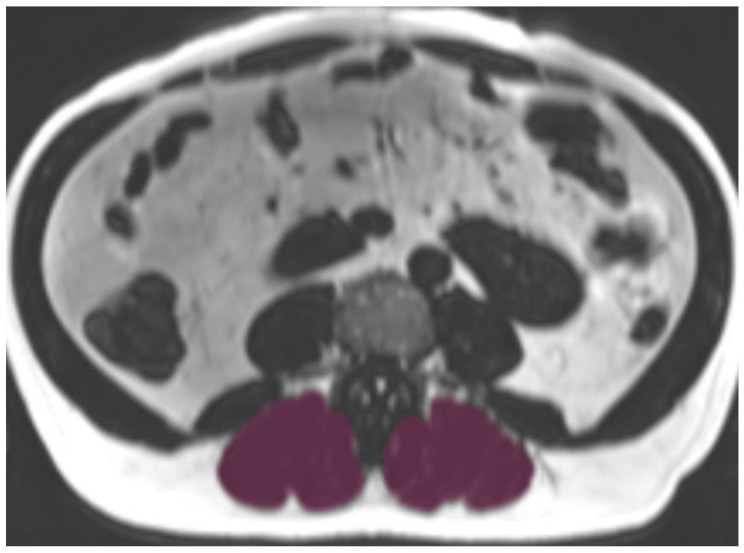

Methods: Within the population-based KORA cohort, 214 participants underwent whole-body magnetic resonance imaging and pulmonary function testing. Paraspinal myosteatosis was quantified by chemical shift-encoded MRI at lumbar vertebra 3 (L3), from which proton density fat fraction (PDFF, in %) maps were derived. Intramyocellular (IMCL) and extramyocellular lipids (EMCL) were determined through voxel-based analysis using validated PDFF thresholds. COPD was defined spirometrically as FEV1/FVC below the lower limit of normal. Associations were examined using multivariable regression models adjusted for age, sex, smoking status, physical activity, and body mass index.